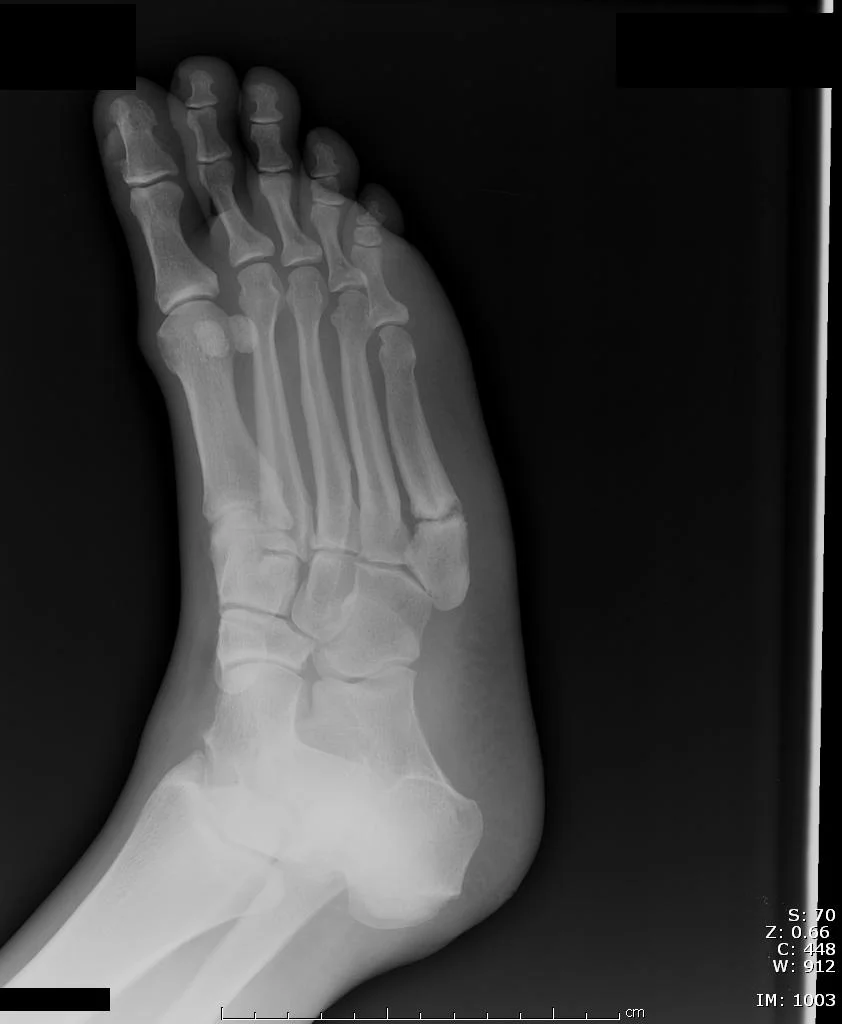

35+ 5Th Metatarsal Bone Fracture Pics. Jones fractures occur in a small area of the fifth metatarsal that receives less blood and is therefore more prone to difficulties in healing. Treatment is either immobilization or surgery depending on location of fracture, degree of displacement, and athletic level of patient.

The base of the fifth metatarsal is located on the outside (lateral) aspect of the foot where you can feel a prominent bone, about half way along the length of the foot. The fifth metatarsal bone is a long bone in the foot, and is palpable along the distal outer edges of the feet. The fifth metatarsal is located on the little toe side (lateral side) of the foot and connects to the it is located 1.5cm distal to the tuberosity of the 5th metatarsal. Two types of fractures that often occur in the fifth metatarsal are: